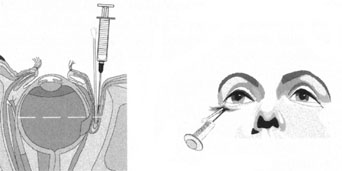

Many patients are most bothered by cataract-induced glare. For these patients, acuity testing under glare situations is indicated. There are several methods to assess visual acuity reduction by glare. The choice of method is often best dictated by the patient's history. If a patient complains of glare problems in the supermarket, or other uniformly illuminated environment, the brightness acuity test can be performed (Mentor Ophthalmics). For this test, the specially illuminated handpiece is held in front of the tested eye using best spectacle correction (Fig. 1). The Snellen acuity is rechecked and can be recorded on each of three light settings.

Patients who complain of glare from point sources of light, such as oncoming headlights or bright sunshine, may be best evaluated by a different form of glare testing. To simulate the environment of the patients' symptoms, Snellen acuity is measured while directing a point source of light obliquely toward the eye outside their best spectacle correction or outside of a phoropter dialed in with their best manifest refraction (Fig. 2).